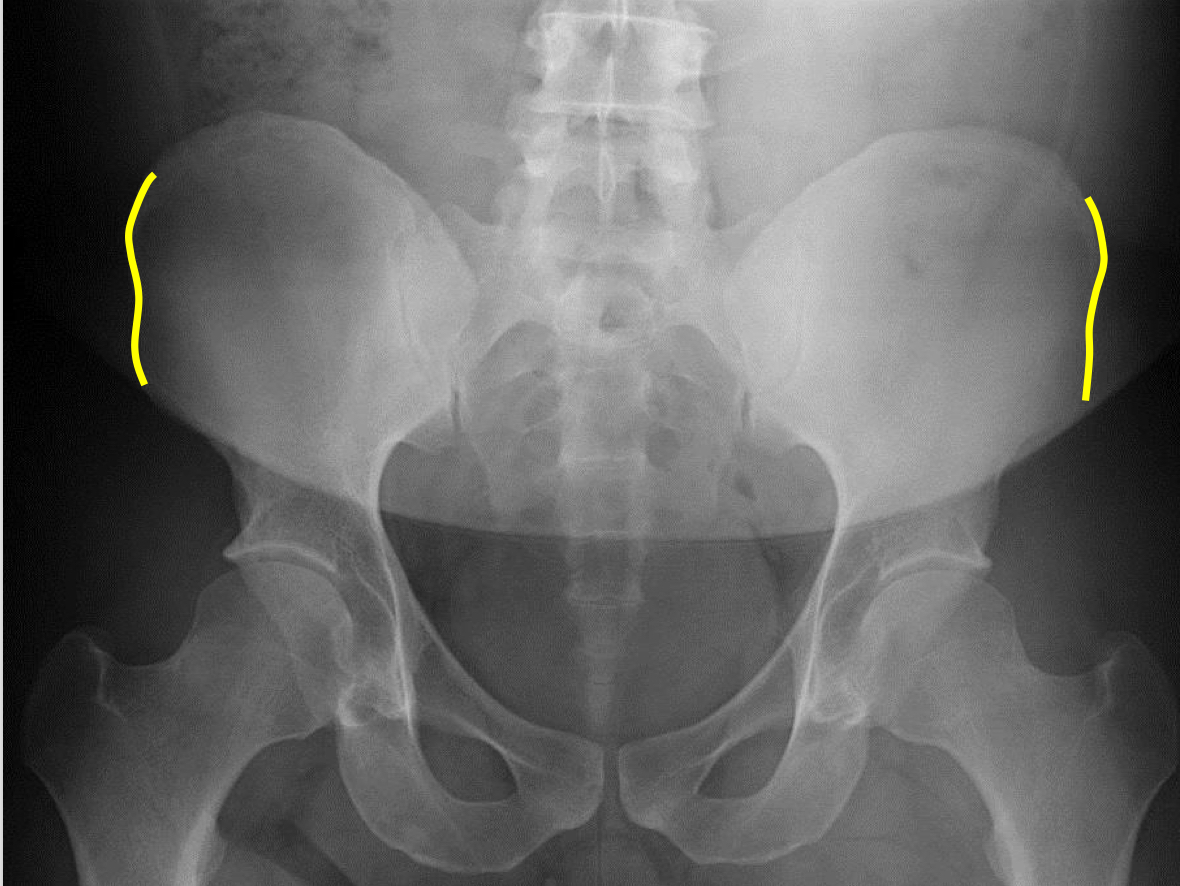

What view is this?

AP (Anterior to Posterior) LumboPelvic

What is this?

Lateral Iliac Crests

What is this?

Ischial Tuberosites

What is this?

Obturator Foramen

What is this?

S2 Tubercle

What is this?

Pubic Symphysis

What is this?

Sacral Groove

What is this?

Lateral aspect of sacrum

What is this?

Medial Aspect of Ilium